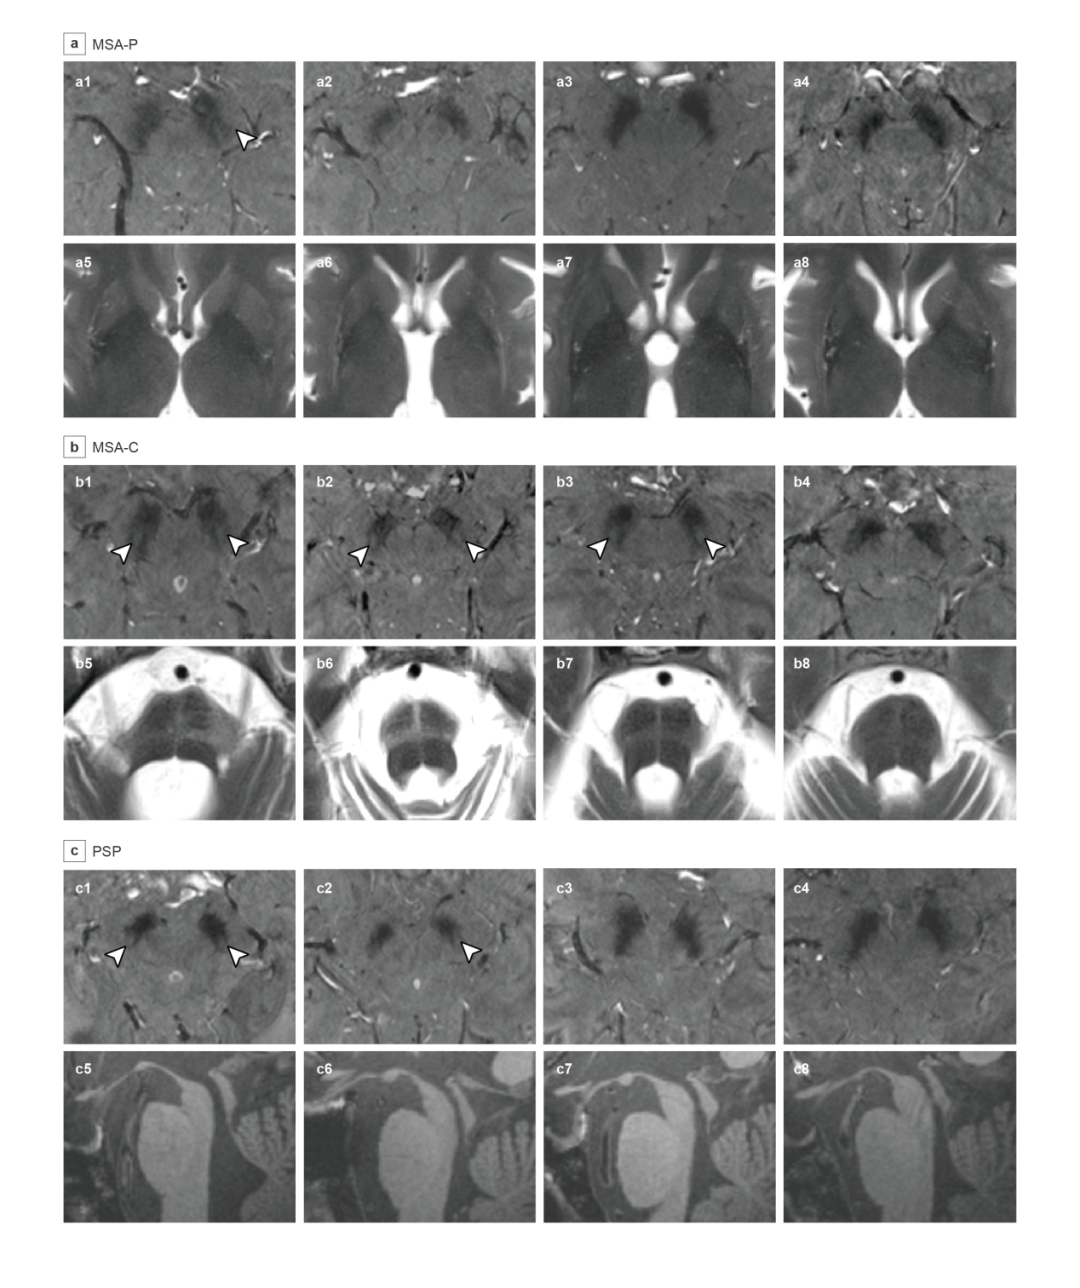

图2 MSA-P、MSA-C、PSP组黑质区域7T 3D T2*图像

采用“6分可见度量表”评分界值为6分来诊断早期PD的敏感度和特异度均为100%。该量表鉴别早期PD和iRBD的受试者工作特征(ROC)曲线下面积为0.940,鉴别早期PD和MSA-C的ROC曲线下面积为0.892。R2分析和基于体素的主成分分析显示,PD和PSP黑质铁沉积主要位于黑质背侧和后部,MSA-P黑质铁沉积主要位于黑质中间部和后部,而MSA-C黑质铁沉积主要位于黑质腹侧(图3)。